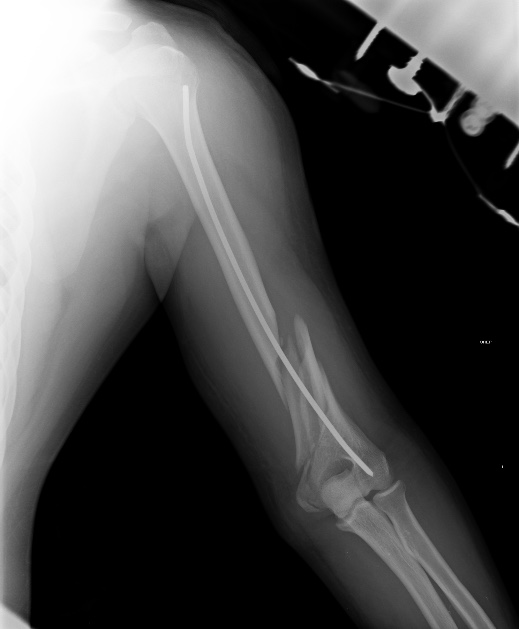

Вот снимки от 17.08.2016, максимально приближенные из имеющихся по дате к реостеосинтезу!

Сейчас уже поезд ушел, но если это переделывать, основная мотивация была бы - выстояние в проксимальном отделе.

Если бы выстояния не было, можно было, например, поверх стержня наложить простенький аппарат и сдавить. С диастазом не надо было уходить из операционной.

Здесь больше похоже на периимплантный перелом чем на несращение.